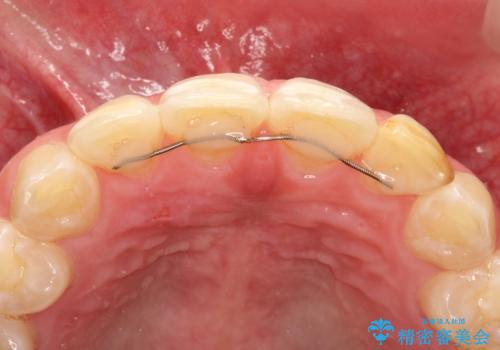

生まれつき歯の色が白濁しているところや、黄色くなっているところがあり、セラミッククラウンに審美的改善を行うこととしました。

ご自身の歯を削る必要がありましたが、セラミッククラウンを装着することで、審美的改善ができました。